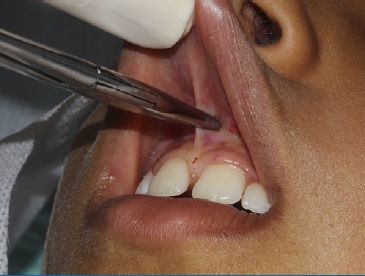

Em seguida, foi realizado o pinçamento na posição apical do freio com a pinça hemostática Kelly e foram efetuadas duas incisões verticais com lâmina de bisturi n.º 15c (Solidor, Brasil) em forma de “v”, com incisão no fundo de sulco até a região da papila interincisiva para a remoção do freio labial superior em nível supra periosteal (Figura 2‑3-4-5).